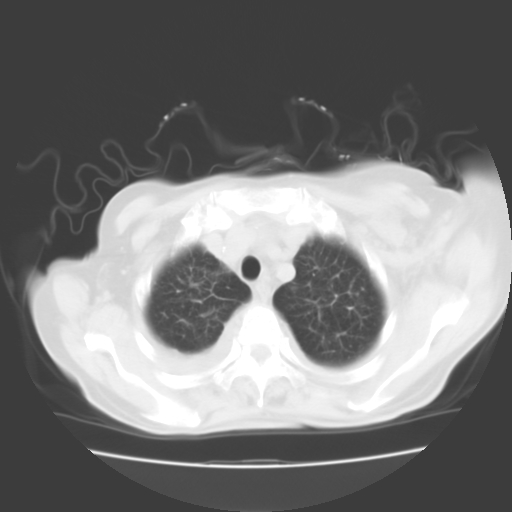

肺部病变为淋巴转移,肝脏转移,及局部淋巴转移。胸水可能为淋巴回流受阻(血性的考虑胸膜转移)

癌性淋巴管炎,肝脏转移,瓷胆囊

1)左侧乳腺癌并左侧腋窝及纵隔淋巴结转移,两肺淋巴道转移(癌性淋巴管炎),肝脏多发性转移。2)双侧胸腔积液。3)慢性胆囊炎。

3、双肺癌性淋巴管炎;

1)左侧乳腺癌并左侧腋窝及纵隔淋巴结转移,肝脏多发性转移。2)双侧胸腔积液伴双肺蝶翼样磨玻璃高密度影,双侧肺门血管影增粗(图像不全,肺门层面没纵隔窗),考虑心功能不全所致。3)慢性胆囊炎伴壁钙化。